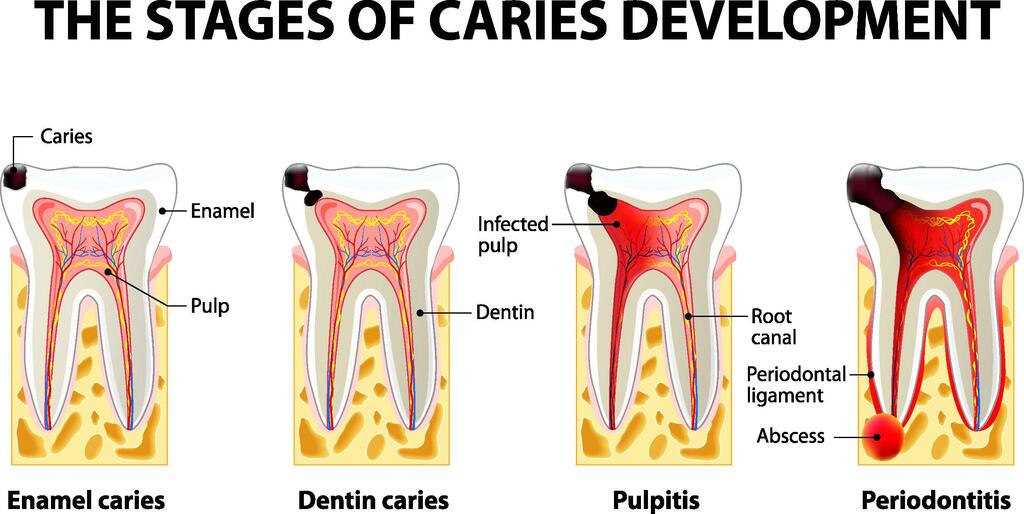

দাঁতের ক্ষয়জনিত কারণ, গোড়া ফোলা এবং পেকে যাওয়া ইত্যাদির ফলে খাদ্যদ্রব্যাদির সঙ্গে নানা ধরনের মারাত্মক রোগের জীবাণু পাকস্থলীতে প্রবেশের সুযোগ পায় এবং এই জীবাণুই পরবর্তীতে দেহের অভ্যন্তরে কঠিন ও সংক্রামক রোগের সৃষ্টি করে। দাঁতের স্বাস্থ্য ভালো থাকলে দেহকে সুস্থ রাখা যায় এ কথা নিঃসন্দেহে প্রমাণিত হয়েছে। পোকা লাগা দাঁতের রোগের নাম ‘ডেন্টাল ক্যারিজ’।

মাড়ির রোগ দীর্ঘদিন পুষে রাখলে যেমন মাড়িতে প্রদাহ বা ইনফেকশন হয় তেমনি দন্তীয় বা ডেন্টাল ক্যারিজ রোগ দীর্ঘদিন বিনা চিকিৎসায় থাকলে দাঁতের গোড়ায় পুঁজ জমা হয়। মুখের এই ধরনের রোগের কারণে যেমন মুখে স্থানীয়ভাবে অসুবিধার সৃষ্টি হতে পারে তেমনি দেহের জন্য বিপদ নিয়ে আসতে পারে। যেহেতু দাঁত ও মাড়ির সঙ্গে দেহের রক্ত চলাচলের সম্পর্ক আছে, তাই ইনফেকশন রক্তের সঙ্গে গিয়ে হৃৎপিণ্ড (Heart), মস্তিষ্ক (Brain), হাড় (Bone) সন্ধি (Joint), বৃক্ক (Kidney),, যকৃৎ(Liver) ও চর্মের ওপরও প্রভাব ফেলতে পারে। মুখের সংক্রমণ জাতীয় এই ধরনের রোগের কারণে যেসব রোগ সৃষ্টি হতে পারে বা রোগটিকে আরও ত্বরান্বিত ও দির্ঘায়ীত করতে পারে, সেগুলো হলো-